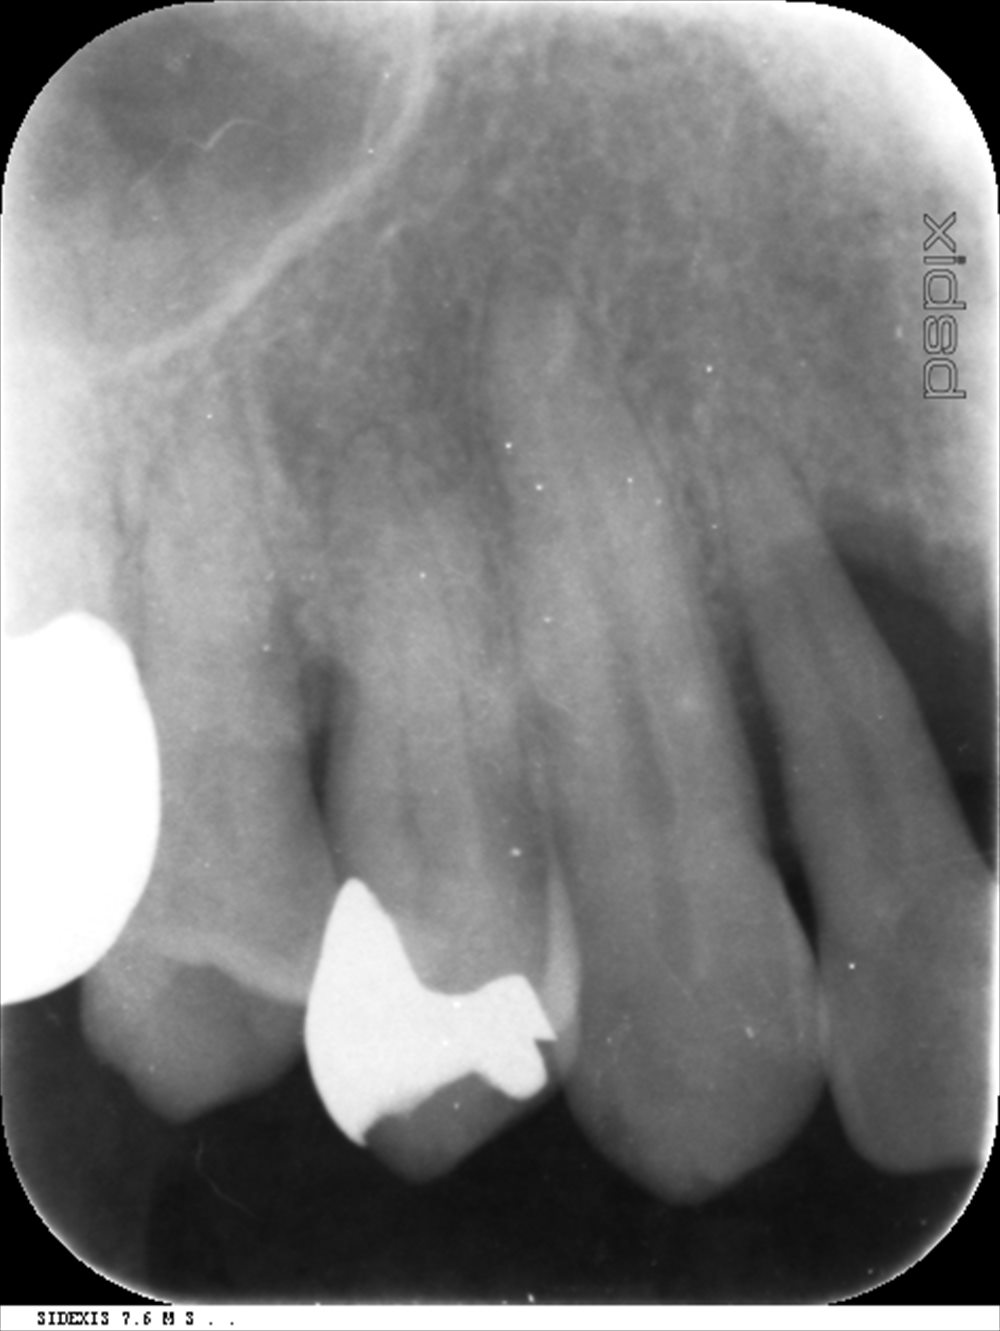

右上の二番目の前歯(腫れている歯)こちらはポケットが12mmあり、骨が根尖付近までなくなっています。